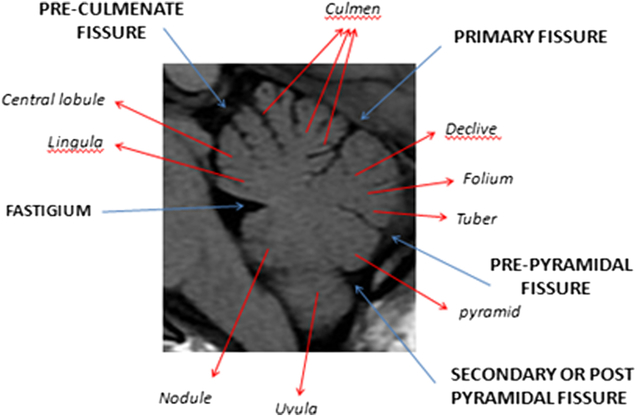

The primary fissure is the first to develop at 14 weeks. The pre-pyramidal and the secondary (post-pyramidal) fissures are seen at 16 weeks (Figure 2). The posterolateral fissure is visible at week 17.Reference Liu, Zhang and Lin2 The earliest studies of gestational age demonstrate that the ratio between the volume of the parts above and the volume of those below the primary fissure is 1:1 until the age of 16 weeks. This will be followed by rapid growth of the pyramid vermis and tuber vermis. The parts beneath the primary fissure grow faster and become larger than the parts above the fissure. Figure 3 illustrates the normal anatomy of the vermis.

Figure 3: Annotated sagittal T1 MRI image of the cerebellum in a healthy teenage volunteer showing normal anatomy and major fissures.